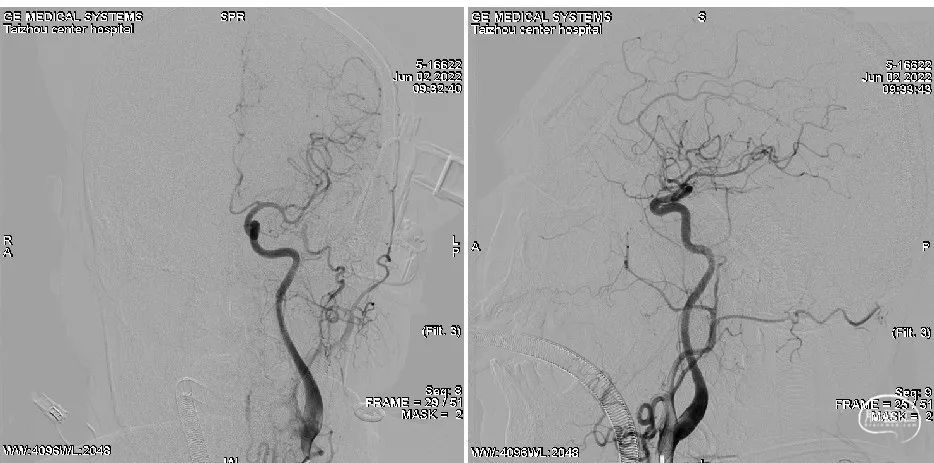

微导丝过病变进入P2远端。

微导管过病变进入P2远端。

中间管抽吸后BA尖再通。

3Max抽吸导管轻松通过左P2段,做一次抽吸。

基底动脉尖、左SCA、P2远端血流恢复。